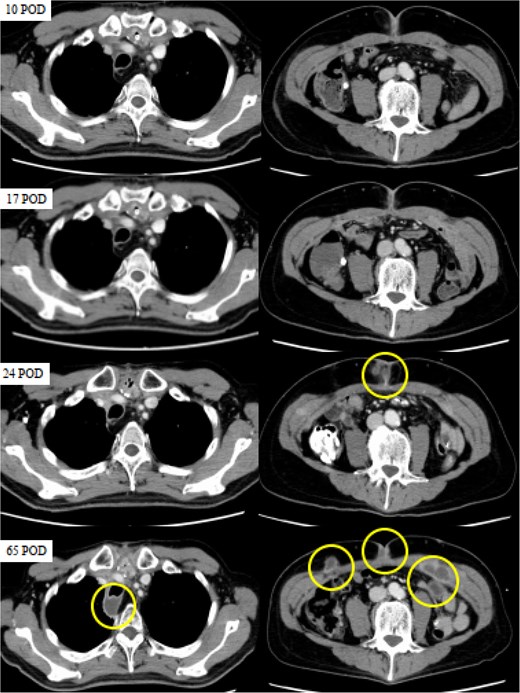

However, a computed tomography (CT) scan performed during an outpatient follow-up on postoperative day 65 revealed multiple abscesses, prompting the patient’s readmission for further management. The abscesses were drained percutaneously; additional cultures, including mycobacterial testing, were conducted to identify the cause. Although the general bacterial and fungal cultures were negative, the mycobacterial cultures were positive on postoperative day 80 (Fig. 2). The general bacterial and fungal cultures were negative; however, on postoperative day 80, the mycobacterial cultures were positive (Fig. 3). Following wound debridement, fever frequency gradually decreased; the patient’s condition improved steadily.

CT images obtained on postoperative days (POD) 10, 17, 24, and 65. The circles indicate abscesses. CT scans were performed on POD 10 and 17 to investigate the high levels of inflammation, but no abnormalities were detected. While no apparent abnormalities were observed on POD 10 and 17, SSI was evident on POD 24, and multiple abscesses had formed in the posterior trachea and abdominal wall by POD 65.